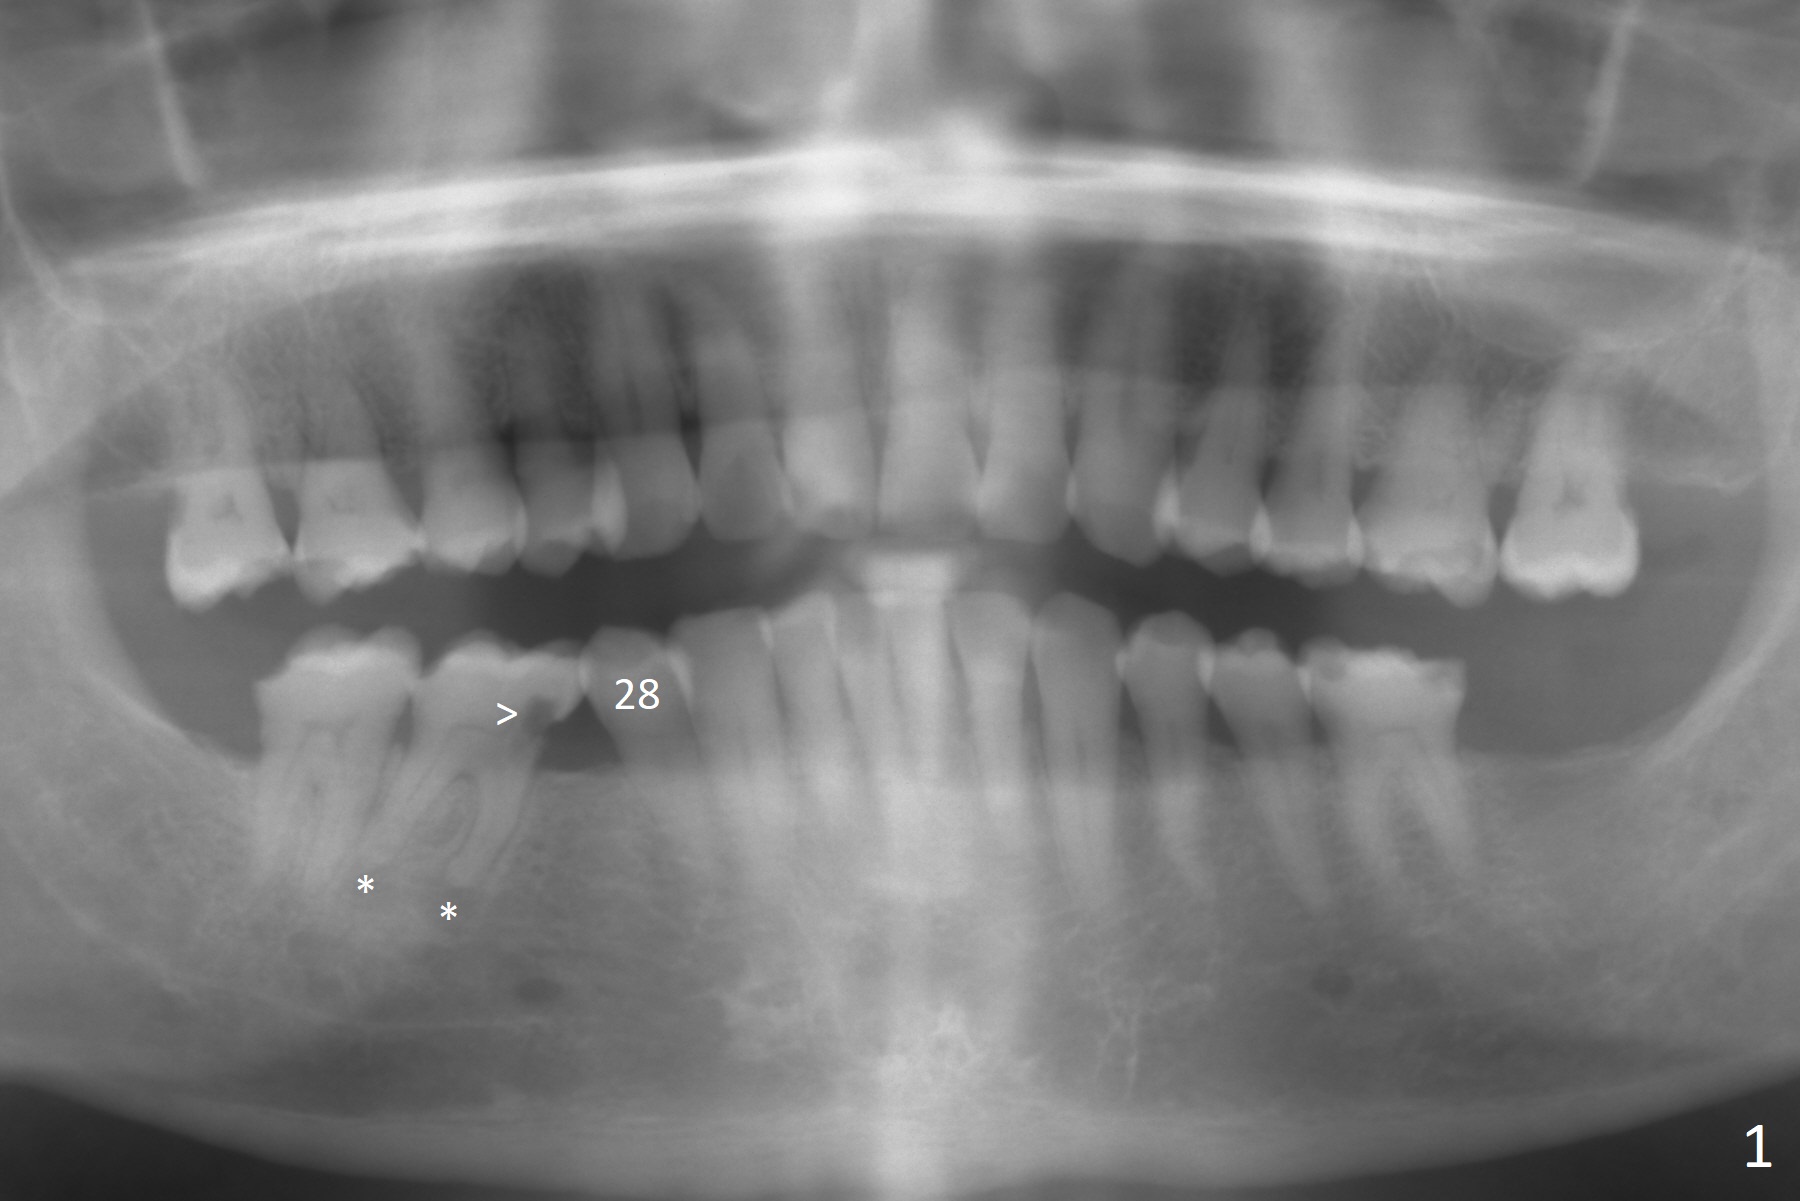

A 58-year-old man has history of temporomandibular joint disorder as related to severe occlusal breakdown and missing tooth #18 (Fig.1,4). The tooth #29 is also missing; the tooth #30 has shifted and tilted mesial. Severe pain develops at #30 two years after MOL composite (Fig.3). The patient insists on extraction and implant, although pulpotomy has been done to alleviate the pain. Although there is sufficient bone height, IS implants will be used because of primary stability and apparent better implant/abutment binding as compared to IBS (with tendency of screw loosening). Osteotomy will be initiated in the mesial socket at #30. Measure the whole length of drills. Find 17-8 mm mark, which will be used as soft tissue landmark.